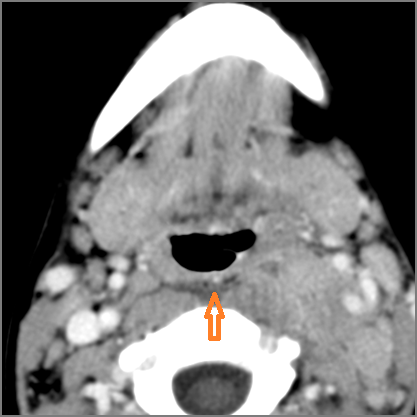

There is gas in the soft tissues.

There is a foreign body separate from or in areas of soft tissue swelling.